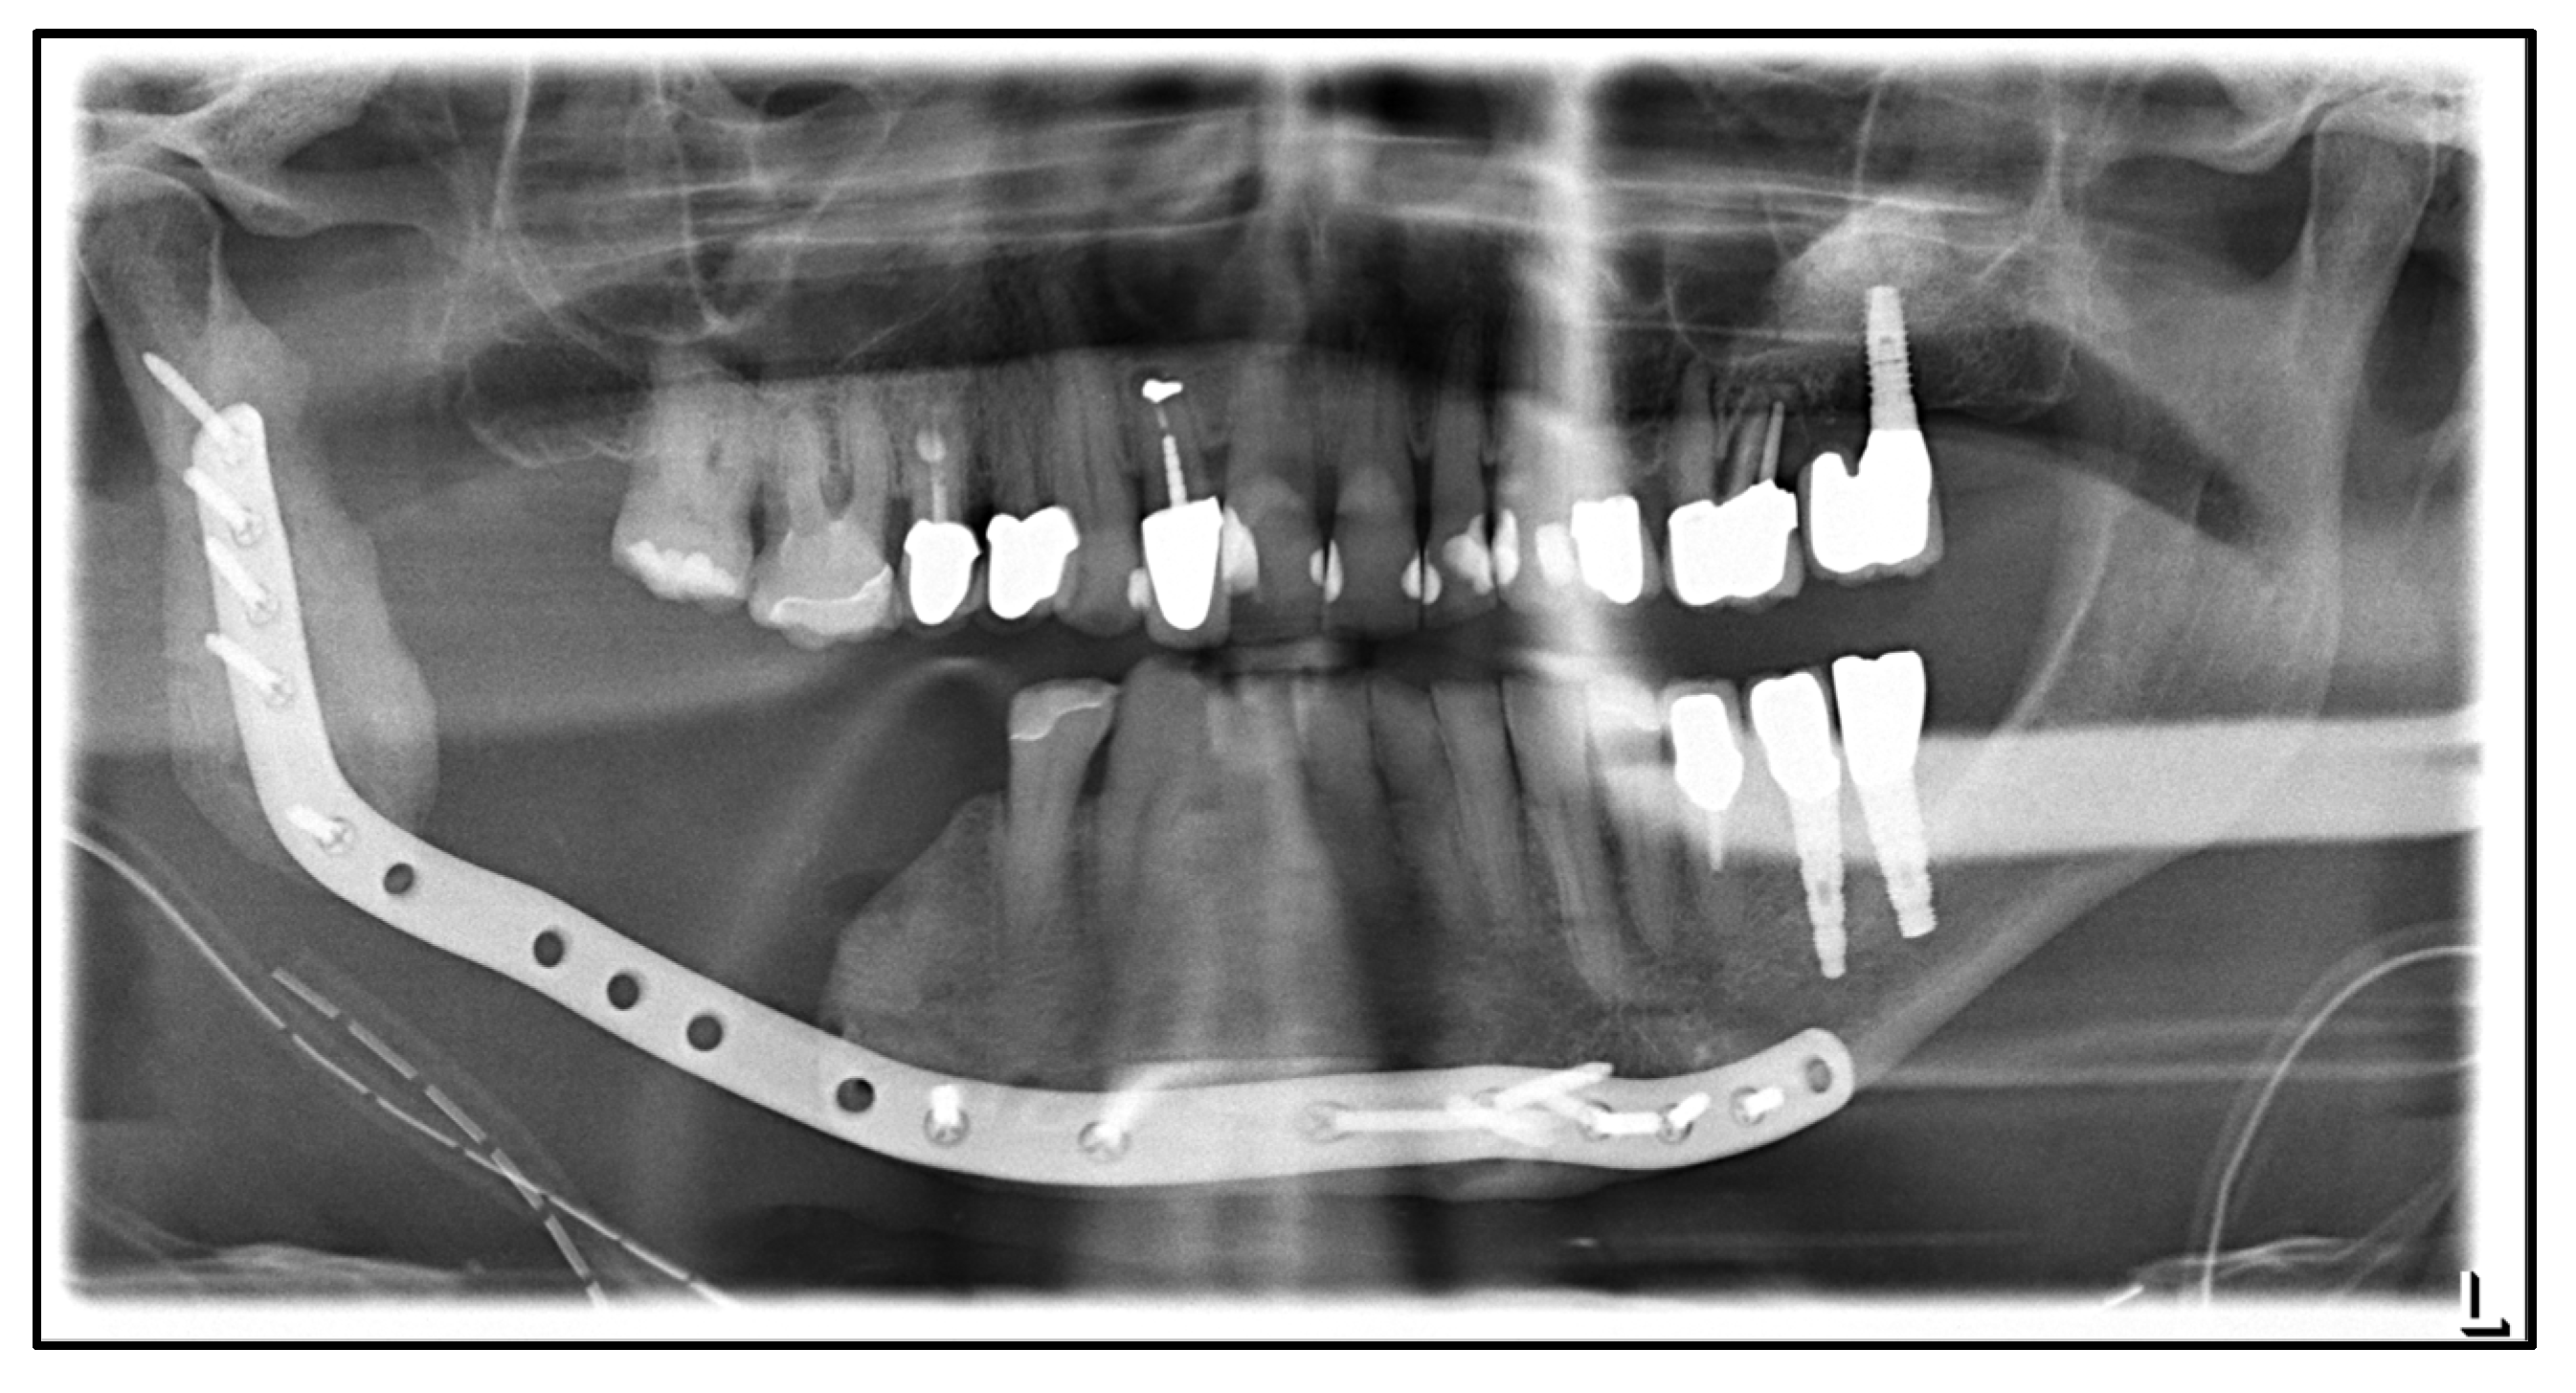

| August 2018: | Partial mandibular resection with continuity defect and alloplastic reconstruction using a patient-specific plate, excision of a submental fistula |

| November 2018: | Cervical abscess on the right side with infected osteosynthesis material. Decortication and partial removal of the PSI. |

| September 2022: | Partial mandibular resection from the left mandibular angle to the right mandible, including the right temporomandibular joint, CAD/CAM-guided reconstruction with a bilateral free scapula flap with skin island, and patient-specific plate. In the course: